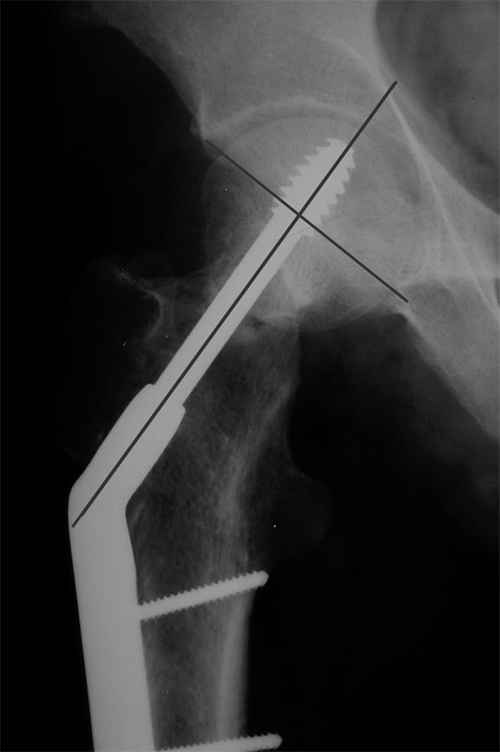

Больной Т. 1966 г.р.Травма 28.06.2007. Прооперирован в г. Бишкек, Оп: Остеосинтез правого бедра системой DHS. В последующем беспокоили периодические боли в правом тазобедренном суставе с иррадиацией в коленный сустав в область передней поверхности правого бедра. Лечился амбулаторно с незначительным эффектом. В 07.04.2008 по 08.05.2008 года лечился в госпитале ГУВД и СО в стационаре с Срастающийся перелом шейки правого бедра в условиях фиксации системой DHS – боли уменьшились.Боли обострились 03.02.2009 внезапно, госпитализирован. Результат - Псевдоартроз шейки правого бедра (имеются косвенные признаки разрушения спонгиозной части головки бедра)Планируется - Работает милиционером. Имеющийся опыт протезирования у данной категории во всех случаях в ближайшее время заканчивался дисквалификацией. Работоспособный возраст (43 года).Наиболее приемлемым и реальным методом лечения предполагается: Удаление конструкций из бедра. Заполнение полости от винта монолитным аутотрансплантатом из крыла (крылев) подвздошной кости. Медиализация большого вертела. Предполагаемый период нетрудоспособности 3-4 мес.

И, видимо, вальгизирующая остеотомия бедра - если в планах все-таки продолжать попытки сохранить собственный сустав. Эндопротезирование более предсказуемый путь.

я говорил о вальгизирующей, использовать клинковую пластину.Проблема уже обсуждалась на форуме. По этому поводу Джолдас Кульджанов выложил что-то вроде микролекции http://weborto.net/forum/1226822410/1227116964/index_html.

Коллеги правы, что надо делать вальгусную остеотомию с латеризацией диафиза бедра. Рекомендуемая медиализация приведет к вальгусной деформации оси конечности.

Предлагамый монолит из-за трудности проведения Special Chisel для клинка не рекомендуется. Место удаленной конструкции забивается спонгиозной костью из крыла, для предупреждения пенетрации в сустав лучше под экраном.